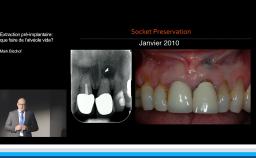

Edentement au secteur anterieur: le défi pour une esthetique optimale

A partir de la description des facteurs de risque esthétique du bloc incisivo-canin maxillaire, de la présence d’os et de gencive autour des implants, le conférencier présente une succession de cas cliniques décrivant ses procédures chirurgicales et prothétiques.

• de déterminer le bon timing de chirurgie implantaire post extractionnelle

• de réfléchir sur la préservation à moyen-long terme de l’os autour des implants